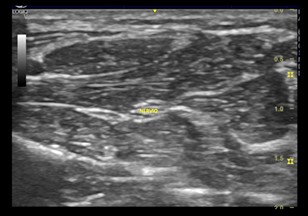

Se observa en la ecografía una red de líneas hiperecóicas finas y paralelas separadas por líneas hiperecóicas, ósea un patrón fibrilar. Los ecos lineales visibles dentro de los tendones dependen de las interfaces acústicas en los límites de los haces de colágeno y los tabiques del endotendineo. Mientras que el epitendineo suele verse como una línea reflexiva que rodea el tendón.

Imagen ecográfica 2.1 Eje longitudinal y transversal de los tendones del músculo flexor de los dedos.

Los tendones poseen gran anisotropía. Ósea los tendones tienen mayor  variabilidad de la ecogenicidad al modificar el ángulo de isonación. Además en comparación con los nervios el tendón posee menos ecos paralelos delgados y densamente empaquetados, es mas circular que oval  y mas móvil durante maniobras de flexión y extensión.